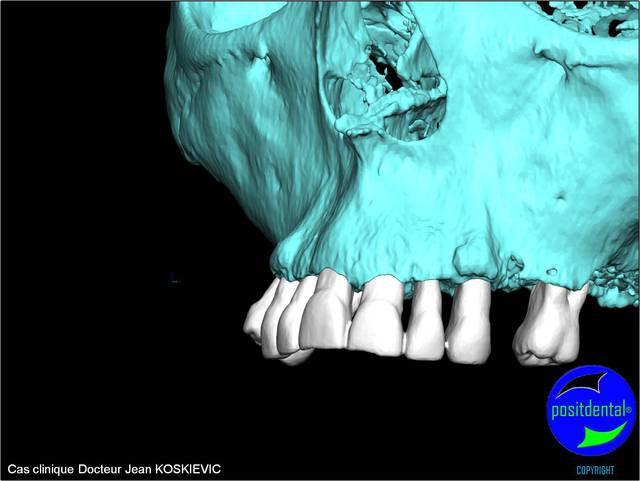

rendu 3D maxillaire sup, pano et photo

Mci - Eugenol